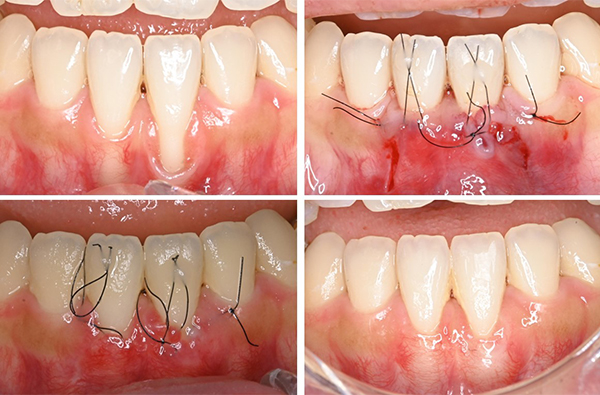

患者一人ひとりの病態やリスク因子を的確に評価し、歯周基本治療を軸とした上で、必要に応じて歯周組織再生療法や歯周形成手術を含めた歯周外科治療を実施しています。

歯周病は慢性的に進行する疾患であるため、短期的な症状改善にとどまらず、長期的な予後を見据えた継続的な管理が重要です。当講座ではメインテナンス・SPTを重視し、治療後の口腔環境の安定と再発予防に取り組んでいます。

臨床では、歯周病の予防から治療、メインテナンス・SPTに至るまでの包括的な歯周病ケアを実践しています。